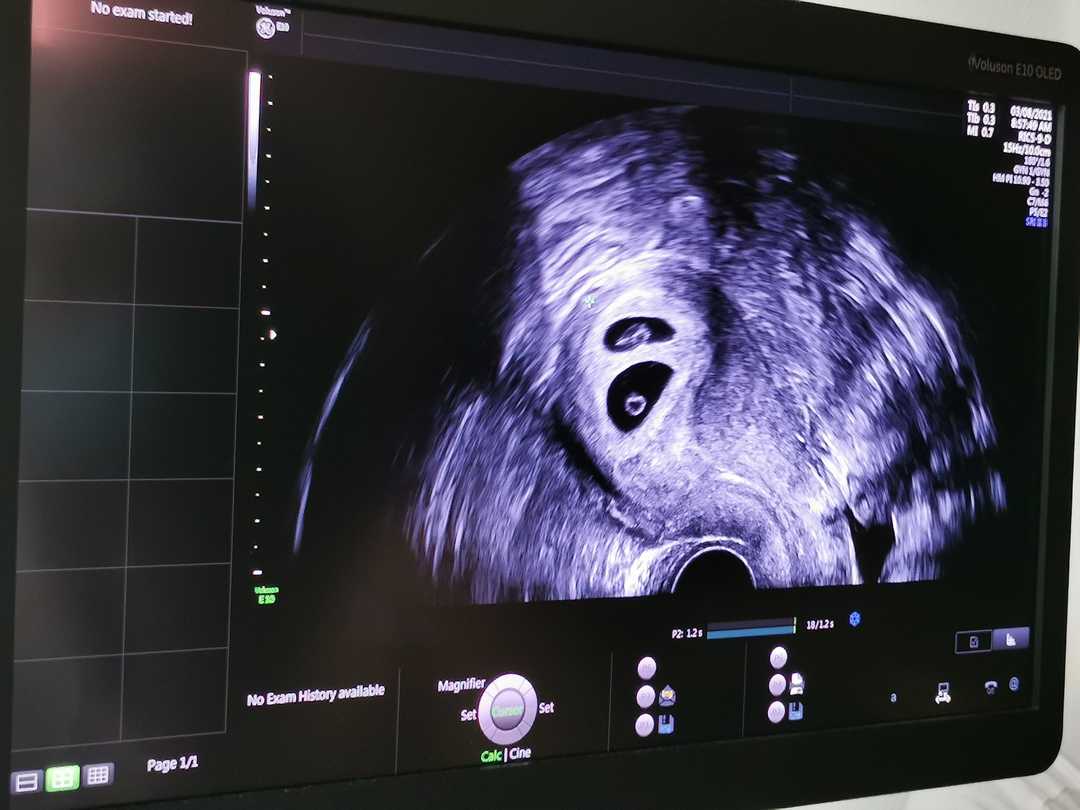

王老师一开始就边给患者检查,边给我详细指导做阴道超声的流程,讲解子宫附件如何定位,如何测量其大小,如何使用B超机上面的键盘,真的好有耐心。她亲自做了两个患者后,便示意让我来做,哈哈,我已经看了几天了,子宫及附件的正常图像及异常图像我都烂熟于心,这下可以大施拳脚,好好展现一下自己的这些日子学习的成果了。

哪里知道一上手,我自己打切面感觉好久都找不到宫颈和子宫(实际上也才几秒钟而已),我一下子就懵了,王老师看出我的紧张和慌张,就握着我的手,手把手地教我定位,这下我有点感觉了。平时看着觉得好简单的,这些图像真是烂熟于心了,没想到自己一上手完全摸不着北。接着下一个王老师就叫我握着她的手感觉探头和电脑屏幕成像之间的关系。然后,她让我自己先做,先测量,做了几个,我慢慢就开始进入状态了。

而且更重要的是我作为妇产科医生第一次拿起超声探头给患者做阴超,对超声有了自己真正的见解,把手里的动作转化为屏幕上的影像,这也是“行”的力量。这种“行”真的让人欢欣鼓舞,让我枯燥的学习生涯一下子亮丽起来。